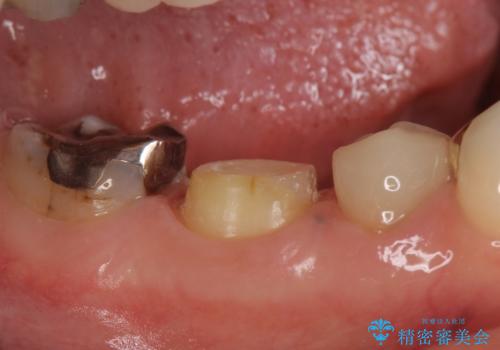

- 右下の奥歯でものを咬むと違和感があるので診て欲しいといらっしゃった方の症例です。

右下6は神経が死んでいたため根管治療を行い、オールセラミッククラウンによる補綴を行いました。

右下7は冷たいものがしみていたため、銀歯を除去後、オールセラミッククラウンによる補綴を行いました。